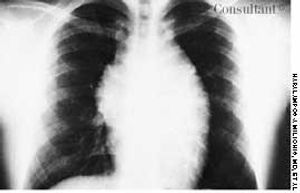

A 19-year-old man was admitted to the hospital with malaise, fatigue, and intermittent fever (temperature of 38°C [100.4°F]) for the last 2 weeks. Physical examination revealed scarce purpuric lesions over the lower extremities; a pericardial friction rub was audible over the precordium when the patient was supine and seated, and the spleen was remarkably enlarged.